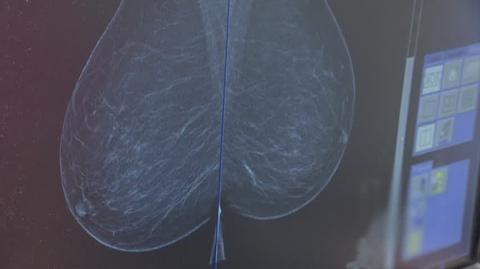

Mammografia - badanie, które może uratować życie

Mammografia - badanie, które może uratować życieTVN24

Dyskusja o tym, dlaczego z badaniami profilaktycznymi nie jest dobrze, towarzyszyła całemu wydarzeniu. Są regiony Polski, w których tylko co druga kobieta zgłasza się na bezpłatną mammografię. - W Polsce notujemy ponad 20 000 zachorowań rocznie na raka piersi - mówi profesor Agnieszka Kołacińska-Wow, chirurżka, Uniwersytet Medyczny w Łodzi. Dodaje, że na całym świecie wzrasta zachorowanie na tę chorobę. - W każdym miesiącu mamy takie chore, które ukrywały to przed rodziną, albo same przed sobą tłumaczyły, że to być może jest jakiś siniak. Doprowadzają do bardzo dużego zaawansowania choroby. Niestety, często już mamy do czynienia z chorobą rozsianą po organizmie - dodaje profesor Piotr Wysocki, kierownik Oddziału Klinicznego Onkologii w Szpitalu Uniwersyteckim w Krakowie.